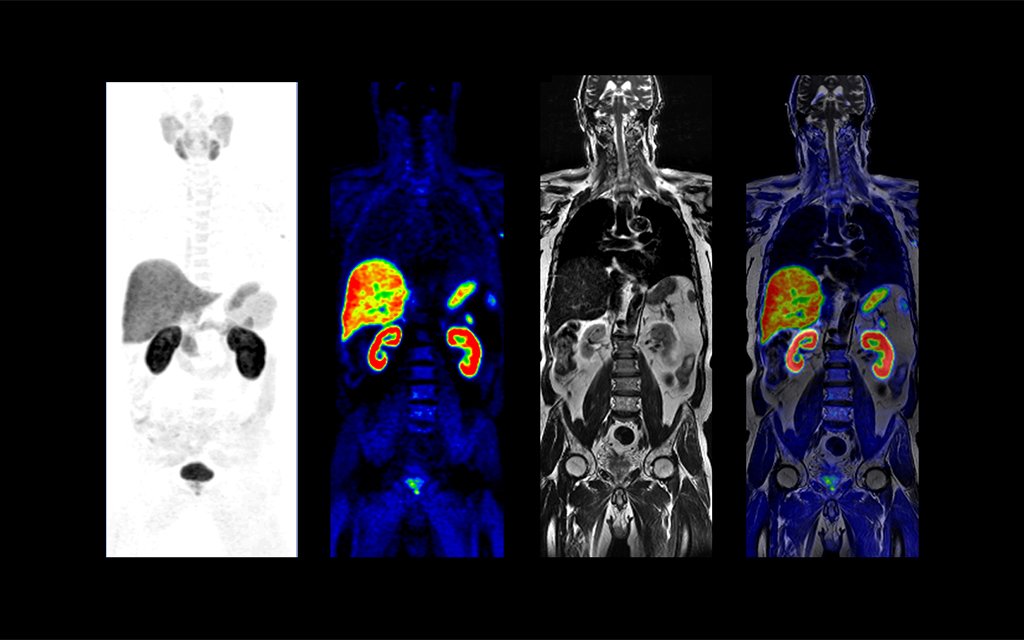

Совмещенное ПЭТ-КТ исследование у пациента с лимфомой позволяет оценить распространенность и активность опухолевого процесса. |